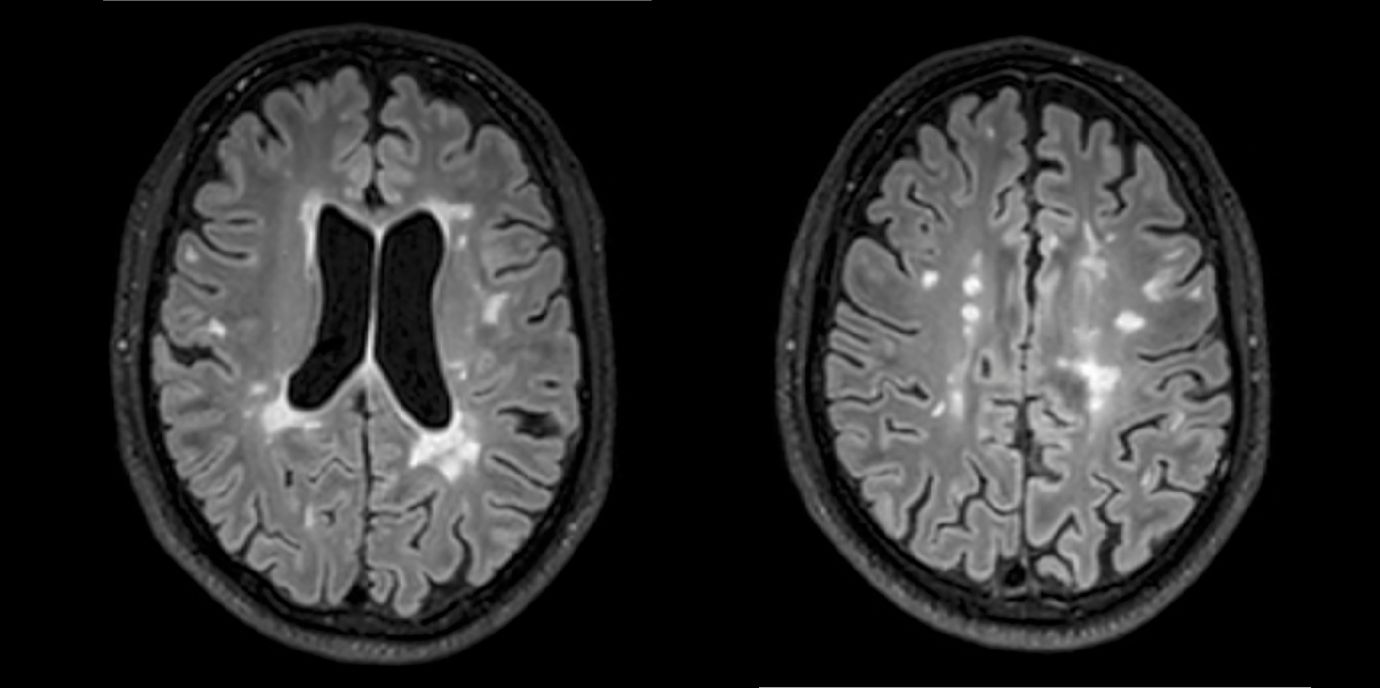

Die Ergebnisse einer neuen Multicenterstudie zu Multipler Sklerose könnten die Therapie dieser chronisch entzündlichen Erkrankung entscheidend verbessern. Forschende der Medizin Unis Innsbruck und Wien sowie des Inselspitals, Universitätsspital Bern belegen, dass zwei oder mehr in der Magnetresonanztomographie (MRT) sichtbare Läsionen im Gehirn innerhalb eines Jahres für eine Therapieintensivierung sprechen. Damit liegen erstmals eindeutige und evidenzbasierte Kriterien für eine Therapieanpassung vor.

Abseits klinischer Symptome, die von Einschränkungen des Sehvermögens bis hin zu Lähmungserscheinungen ein breites Spektrum umfassen, kann die Krankheitsaktivität bei MS auch bildgebend dargestellt werden. „Der Nachweis entzündlicher Läsionen im Gehirn mittels MRTerlaubt auch eine Einschätzung geringerer Krankheitsaktivität, denn vermeintlich stabile Patient:innen können trotz Therapie weiterhin neue, klinisch stumme, entzündliche Veränderungen entwickeln“, weiß Neuroimmunologe Harald Hegen, der an der Innsbrucker Univ.-Klinik für Neurologie bereits seit vielen Jahren zu MS forscht.

In die Studienkohorte wurden 131 MS-Patient:innen aus MS-Zentren in Österreich und der Schweiz eingeschlossen, die unter einer gering- bis moderat-effektiven Immuntherapie zwölf Monate lang klinisch stabil waren und dann einer MRT unterzogen wurden. „Wir konnten zeigen, dass Patient:innen mit schubförmiger MS, die unter Immuntherapie zwei oder mehr neue entzündliche MRT-Läsionen innerhalb eines Jahres entwickeln, auch bei klinischer Stabilität, also ohne Symptome, von einem Wechsel auf eine hoch-effektive Immuntherapie profitieren“, beschreibt Erstautor Gabriel Bsteh von der Medizinischen Universität Wien die zentrale Erkenntnis. Damit liefert die Studie eine für den klinischen Alltag wichtige Erkenntnis, die für die individuelle Therapieanpassung genutzt werden sollte.

„Nachdem Läsionen oft schon vor dem Auftreten klinischer Symptome in der MRT sichtbar sind, ermöglicht eine bildgebende Kontrolle bei Patient:innen mit einer gering- bis moderat-effektiven Therapie ein frühes Eingreifen in den individuellen Krankheitsverlauf“, betont Studienleiter Harald Hegen. In der Studienkohorte waren rund 40 Prozent der Patient:innen klinisch stabil, zeigten allerdings in der MRT schon eine oder mehrere Läsionen. Bislang war in der klinischen Praxis eine Therapieverstärkung nur nach Auftreten klinisch manifester Symptome angezeigt.